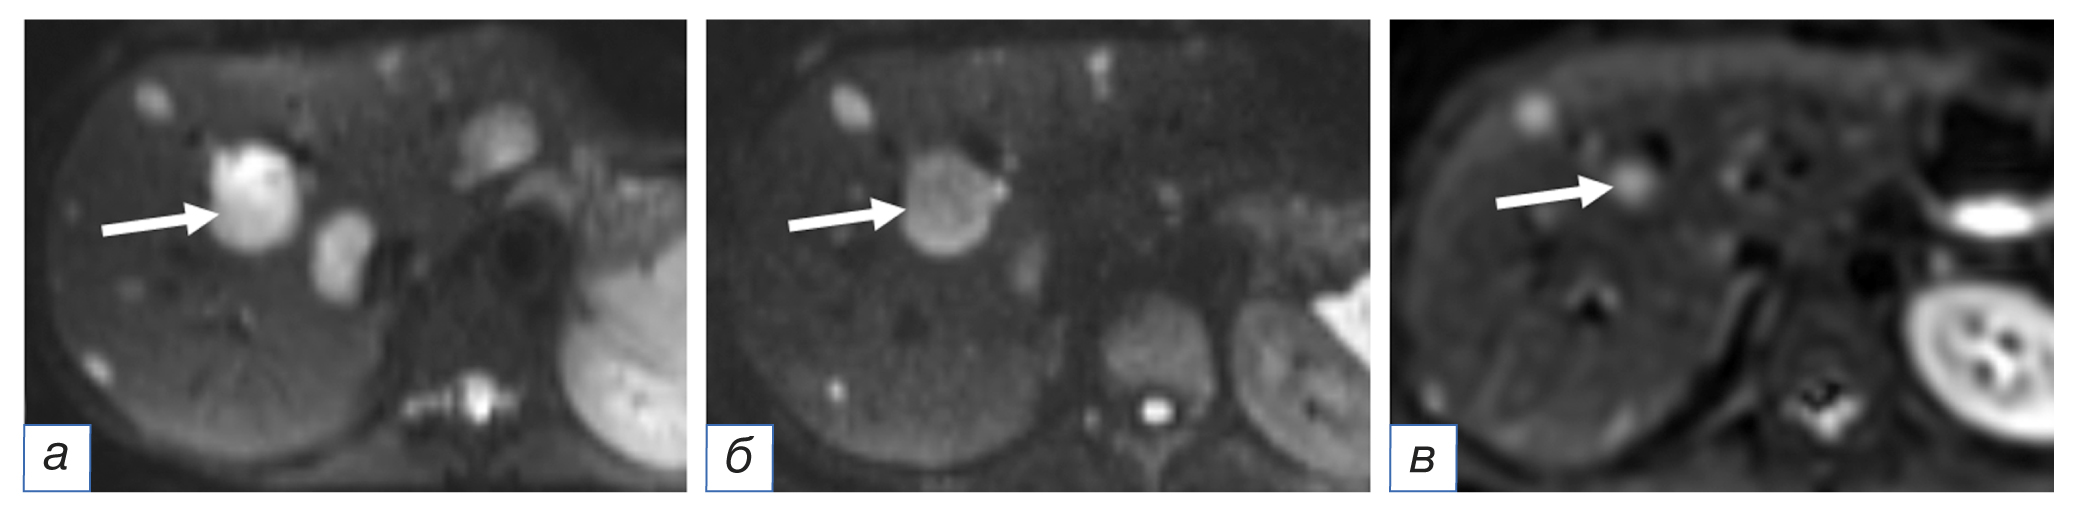

Рис. 3. Пациентка, 28 лет, нейроэндокринный рак тонкой кишки, первичный очаг не удалён: а — магнитно-резонансная томография в режиме ДВИ до трансартериальной химиоэмболизации демонстрирует множественное очаговое поражение печени (контрольный очаг обозначен стрелкой); б — через 16 недель после трансартериальной химиоэмболизации отмечается регресс части очагов, уменьшение в размерах контрольного очага (стрелка); в — через 4 года после повторной трансартериальной химиоэмболизации полного регресса очагов не достигнуто, контрольный очаг уменьшился на 80% (стрелка), прогрессирования нет.

Fig. 3. A 28-year-old female patient with neuroendocrine cancer of the small intestine, the primary focus has not been removed: Magnetic resonance imaging in the DW Iregime before transarterial chemoembolization (а) demonstrates multiple focal lesions of the liver (the control focus is indicated by an arrow); 16 weeks after transarterial chemoembolization (б), the regression of some of the foci, and a decrease in the size of the control lesion (arrow) are noted; 4 years after repeated transarterial chemoembolization (в), the complete regression of lesions had not been achieved, the control lesion decreased by 80% (arrow), there was no progression.